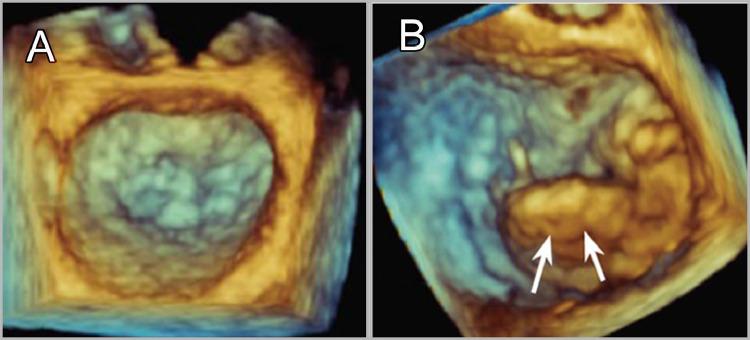

Italian Society of Cardiovascular Echography (SIEC) Consensus Conference on the state of the art of contrast echocardiography.意大利心血管超声学会(SIEC)关于超声造影技术现状的共识会议

Ital Heart J. 2004 Apr;5(4):309-34.